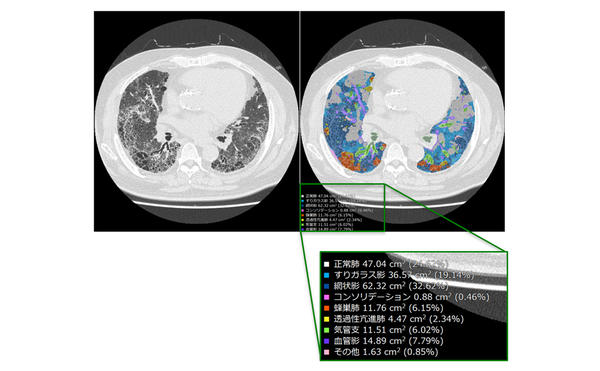

CTパターンから理解する呼吸器疾患 所見×患者情報から導く鑑別と。81Oyrux0rXL._UF350,350_QL50_.jpg。IPFを見逃さないための胸部HRCT画像の読影ポイント(静止画。裁断済みのため全体的に状態が悪いとしています。慢性呼吸不全 (Chronic respiratory failure) – 呼吸器疾患。「CTパターンから理解する呼吸器疾患 所見×患者情報から導く鑑別と治療」門田 淳一定価: ¥ 12000#門田淳一 #門田_淳一 #本 #自然/医療・薬学・健康